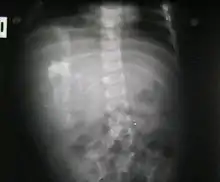

جنين داخل الجنين (بالإنجليزية: Fetus in fetu) هو عيب خلقي فيه تتكون كتلة من الأنسجة تشبه الجنين داخل الجسم. وقد وصف جورج وليام يونغ مثالا لهذه الظاهرة في عام 1808.[1]

هناك نوعان من نظريات المنشأ بشأن "الجنين داخل الجنين". نظرية تعتبر أن الكتلة تبدأ كجنين طبيعي ولكنه أصبح مغلف داخل توأمه.[2] والنظرية الأخرى تعتبر أن الكتلة هي ورم مسخي متطور للغاية. يحدث "الجنين داخل الجنين" بنسبة 1 لكل 500,000 ولادة حية.[3]